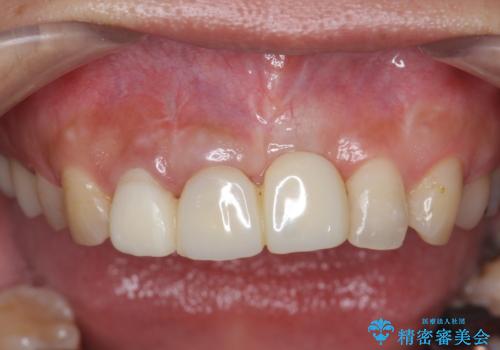

- 前歯の見栄えの悪さの改善を求めて来院されました。

左側の前歯には他院で埋入されたポジションの悪いインプラント補綴により歯冠長の長いクラウンが装着されており、感染による排膿も認められこのまま審美性を改善するのは難しい状態です。